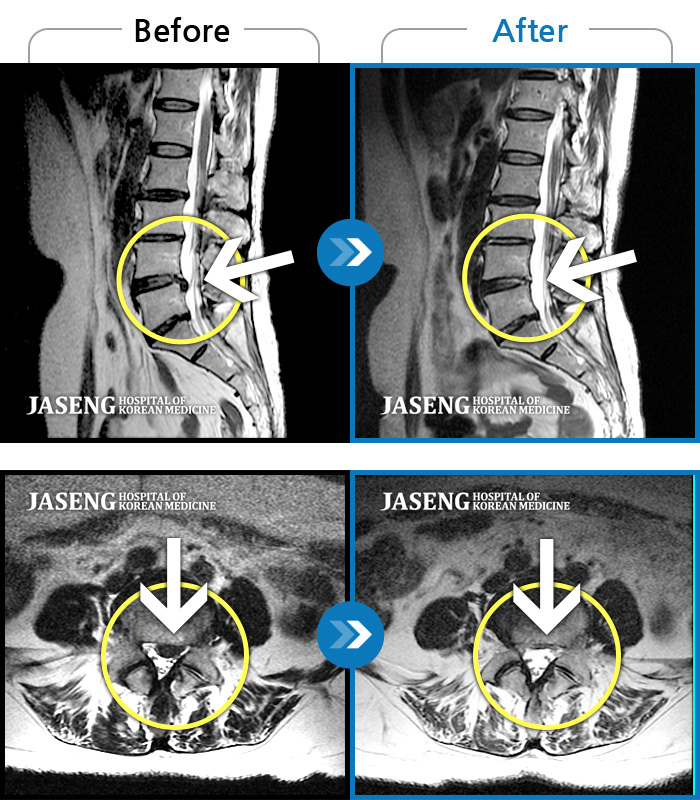

[뱸] 19.11.28~25.05.06